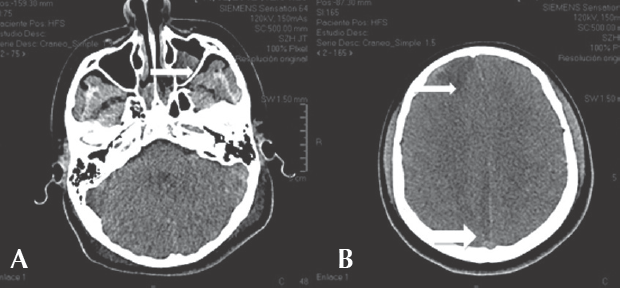

La tomografía de control a los 8 días sugirió una adecuada respuesta al tratamiento antimicrobiano (Figura 3) por lo que se determinó que no requería drenaje intracraneal y sólo se realizó cirugía endoscópica de senos paranasales con drenaje de senos etmoidales. El informe de patología reportó sinusitis frontal etmoidal crónica quística bilateral sin eosinofilia. Egresó después de 38 días de tratamiento antibiótico con triple esquema. La exploración únicamente con he-miparesia izquierda que remitió posteriormente.